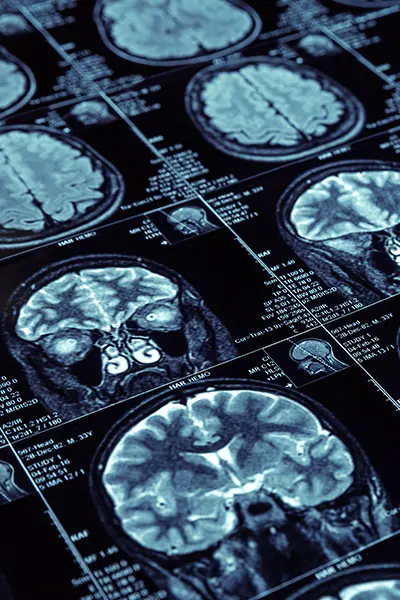

Надішліть якісні фото або сканкопії Ваших медичних документів та знімки МРТ або КТ для онлайн консультації.